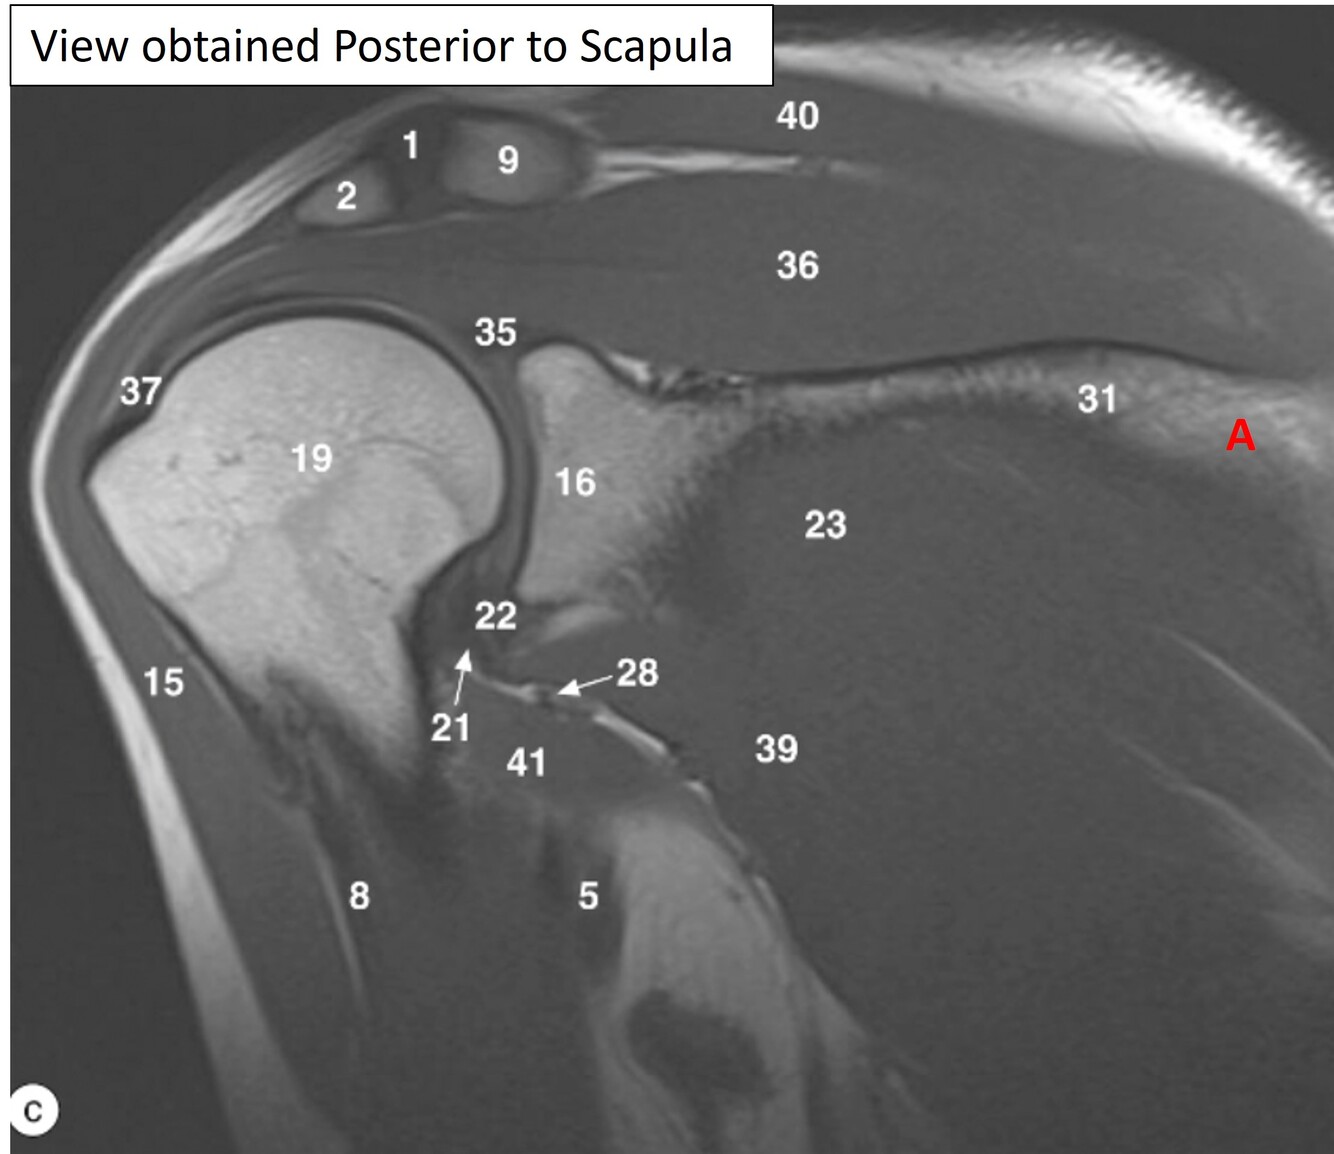

Label 1,2,9,15,36,40

1=Rt. AC joint

2=Rt. Acromion of scapula

9=Rt. Clavicle (acromial end)

15=Rt. deltoid muscle

36-Rt. supraspinatous muscle

40=Rt. trapezius muscle

Label 23, 31,36,39,40

23=Rt. infraspinatus muscle

31=Spine of rt. scapula

36-Rt. supraspinatus muscle

39=Rt. teres minor

Label a

Supraspinous fossa